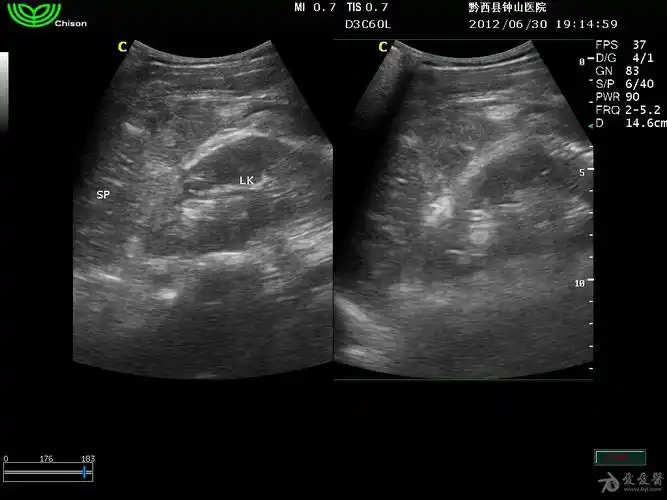

半夜来的脾破裂

脾破裂

腹部超声 | 创伤性脾破裂的超声诊断-大为b超彩超机厂家

脾破裂4小时无肿大

1小时前做的脾破裂出血

超声入门贴305脾破裂

迟发性脾破裂10月4日更正